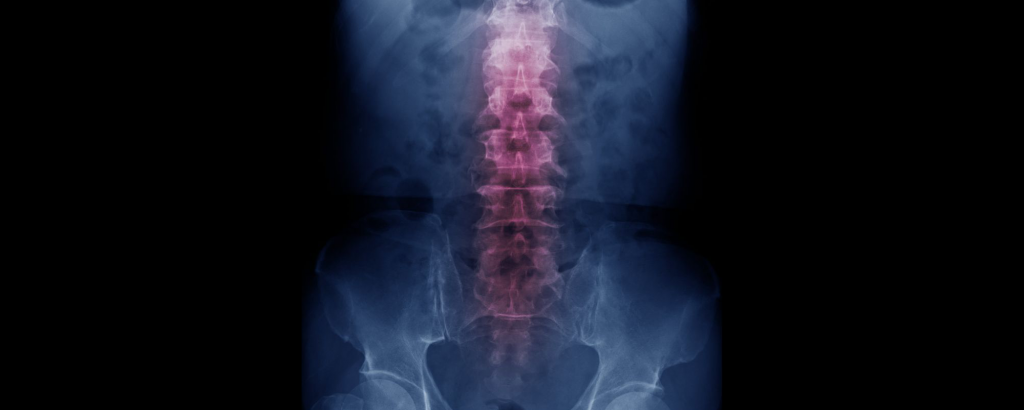

The spinal cord is a long column of nerves passing from the brain to the lower back and through the spinal canal. It provides an integral function, transmitting signals between your brain and everything else, influencing tactile sensation and the operation of limbs and organs.

An injury affecting the middle of the back may result in paraplegia, which affects how the legs function. An injury to the neck can result in quadriplegia, which affects not only the legs but also the arms and chest.

Naturally, the severity of these injuries will vary. Severity is divided by practitioners into two major categories — complete and incomplete. Complete spinal injuries eliminate all sense of feeling and movement below the area of injury. For an incomplete injury, the patient will have some sensation and may be able to move the area partially, and may recover other bodily functions with time.